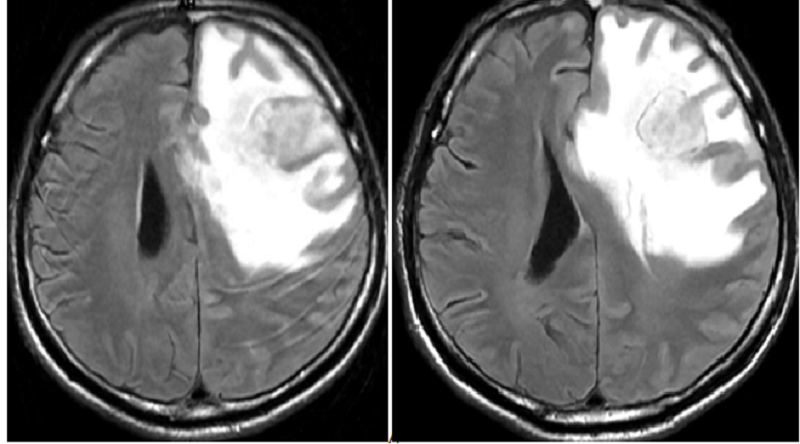

MRI sọ não cho thấy não phù nhiều

MRI sọ não phát hiện tổn thương ngấm thuốc hai bán cầu và tổn thương màng não

Phát hiện nhiều nốt tổn thương ngấm thuốc hai bán cầu và tổn thương màng não